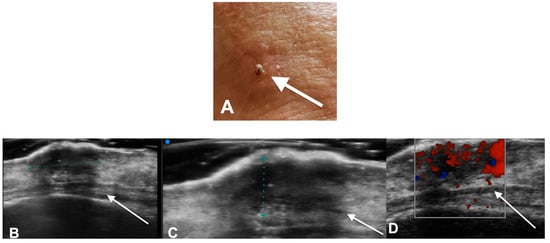

- Reginelli, A.; Belfiore, M.P.; Russo, A.; Turriziani, F.; Moscarella, E.; Troiani, T.; Brancaccio, G.; Ronchi, A.; Giunta, E.F.; Sica, A.; et al. A Preliminary Study for Quantitative Assessment with HFUS (High- Frequency Ultrasound) of Nodular Skin Melanoma Breslow Thickness in Adults Before Surgery: Interdisciplinary Team Experience. Curr. Radiopharm. 2020, 13, 48–55. [Google Scholar] [CrossRef]

- Belfiore, M.P.; Reginelli, A.; Russo, A.; Russo, G.M.; Rocco, M.P.; Moscarella, E.; Ferrante, M.; Sica, A.; Grassi, R.; Cappabianca, S. Usefulness of High-Frequency Ultrasonography in the Diagnosis of Melanoma: Mini Review. Front. Oncol. 2021, 11, 673026. [Google Scholar] [CrossRef]